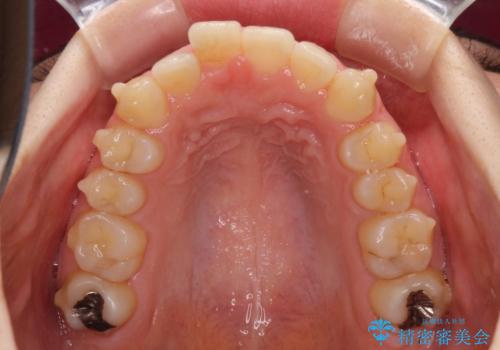

- 口の閉じにくさと割れてしまった奥歯を気にして来院された患者様です。

IPR(歯と歯の間を削る)と歯列全体の後方移動によって口元が引っ込むように設計し、インビザラインにより治療を行うこととしました。

割れてしまった奥歯は抜歯し、矯正治療中の良いタイミングでインプラントを埋入することとしました。

上下正中がずれていたため、抜歯による矯正治療も検討しましたが、口元がそれほど突出していなかったため、非抜歯にて矯正することになりました。

その結果正中のズレは残りましたが、口を閉じたときの感覚や奥歯の咬み合わせには全く問題なく、患者様には大変満足していただきました。